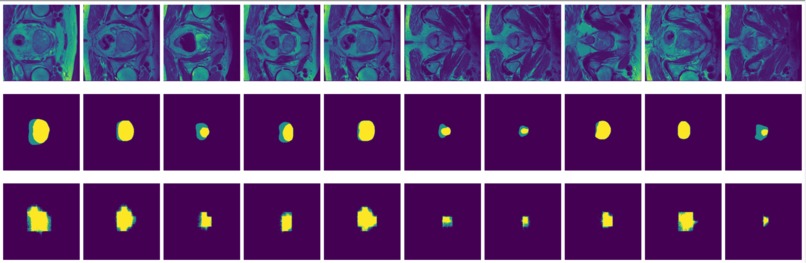

Figure 3: MRI slices (first and thrid rows) from one study with labels (second and fourth rows).

The prostate data set was acquired at Radboud University Medical Center, Nijmegen Medical Centre, Nijmegen, The Netherlands. It consists of 48 prostate multiparametric MRI (mpMRI) studies, 32 of them have corresponding region-of-interest (ROI) targets (background= 0, TZ= 1 and PZ= 2). Each study contains approximately 15 to 20 slices of MRI images, resulting in 602 images in total. Figure 3 shows the 20 slices from one study. The first and last few MRI slices contain little segmentation information. Therefore, to simplify the problem, we will discard the first and last 5 MRI slices from each study. We will use 10 studies (95 images) as the test set and the remaining 22 studies (187 images) as the training set.